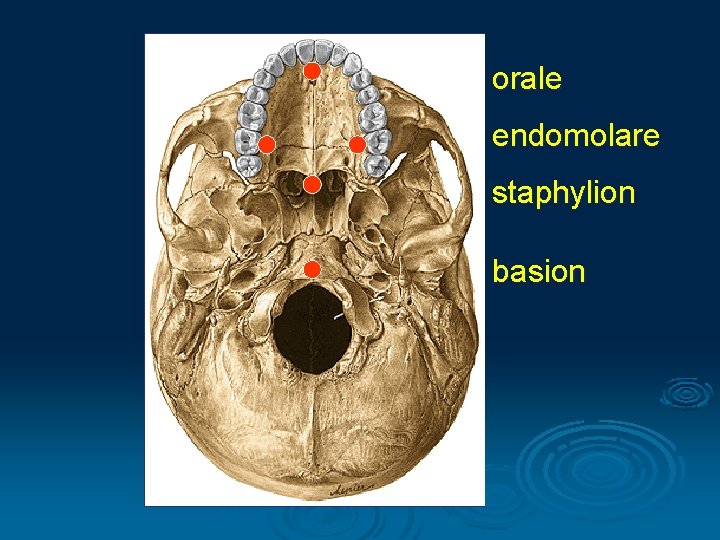

I. Cranimetry Points § Unpaired: nasion, glabella, bregma, akanthion, lambda, orale, opisthocranion, basion, staphylion § Binate: pteryon, porion, euryon, zygion, gonion, endomolare

orale endomolare staphylion basion

Size of the palatum Width: endomolara - endomolare Length: orale - staphylion